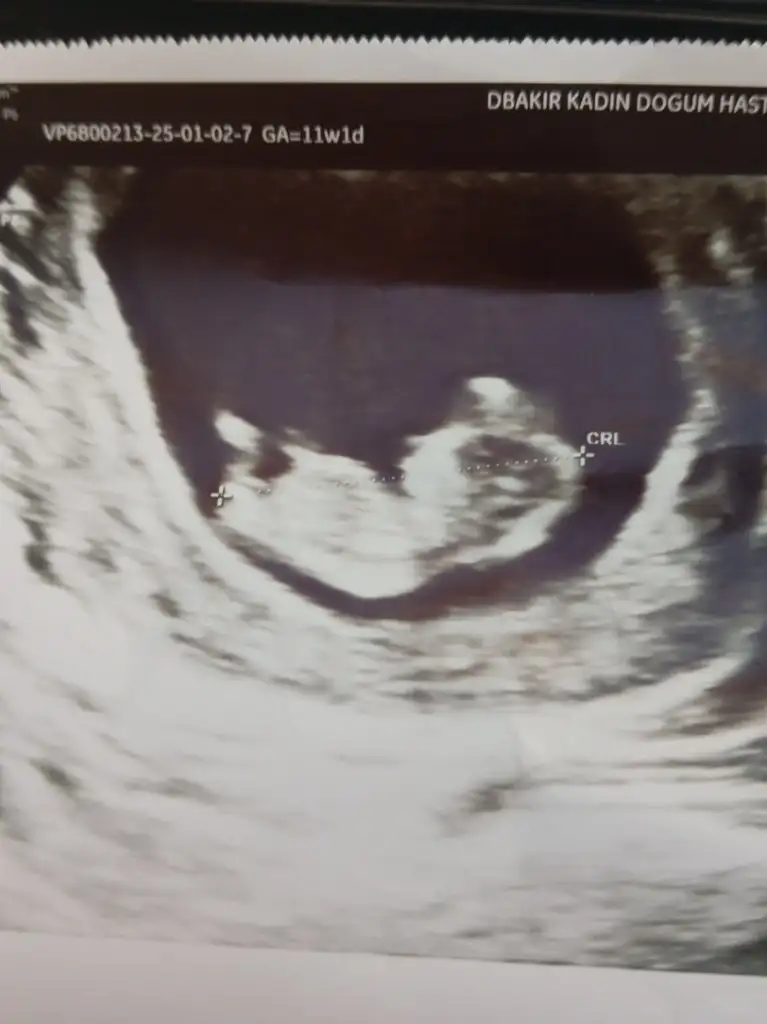

11 haftalık resimde kız bebek gibi canımAnlıyorsaniz benimkine de bakarmisiniz aceba

Bende tahmin alabilir miyim 7 haftalık karından ultroson11 haftalık resimde kız bebek gibi canım